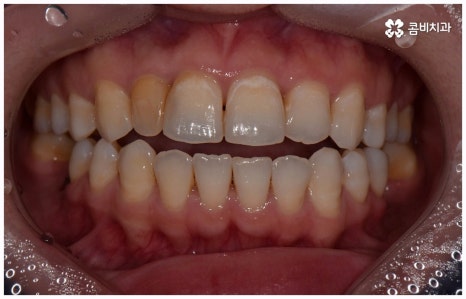

사람의 치아는 유치에서 영구치로 바뀌고 나면 다시 새롭게 나지 않기 때문에 만약 충치 등 구강 질환이나 노환, 외부 사고로 인해 치아를 잃게 되면 이를 대체해 줄 필요가 있습니다. 저작 기능을 담당하고 있기 때문에 치아가 없으면 매일 식사를 할 때 불편함이 크고 발음이 부정확해 질 수도 있으며 양치질을 할 때도 음식물 찌꺼기가 잘 끼는 등 위생 문제가 생길 가능성도 있어요. 또한 앞니 같이 잘 보이는 위치에 있는 치아를 상실하였을 경우 심미적으로도 자신감이 떨어질 수 있는데다 치아 상실 후 시간이 오래 지나도록 그대로 방치하게 되면 주변 치아들이 해당 부위 쪽으로 기울어지게 되고 잇몸뼈 역시 흡수가 일어나기 시작하기 때문에 옆 치아도 내려가면서 치열이 불규칙하게 바뀔 수 있습니다. 결국 심한 경우 상악과 하악의 불균형 및 안면비대칭까지 유발할 수 있기 때문에 치아가 빠졌을 때는 인공 치아를 통해 기능적 심미적인 대체를 해 줄 필요가 있는데요.

이러한 치아 상실에 대해 예전에는 틀니와 브릿지 시술을 많이 받았지만 요즘 대세는 임플란트 식립이라고 할 수 있어요. 틀니처럼 탈락의 위험이 잦거나 음식을 먹을 때 제약이 크게 따르지 않으며 브릿지처럼 양 옆 치아를 제거하지 않아도 되는 임플란트는 치아가 빠진 잇몸에 직접 티타늄 인공 치근(픽스처)을 심은 다음 지대주(연결 부위)를 이어주고 크라운(치아 머리 보철물)을 씌워 수복을 하는 것이기 때문에 저작 능력의 회복이 탁월하고 겉에서 봤을 때 거의 자신의 치아와 다름없이 자연스럽게 보인다는 장점으로 인해 많은 분들이 선호하시는 거예요.